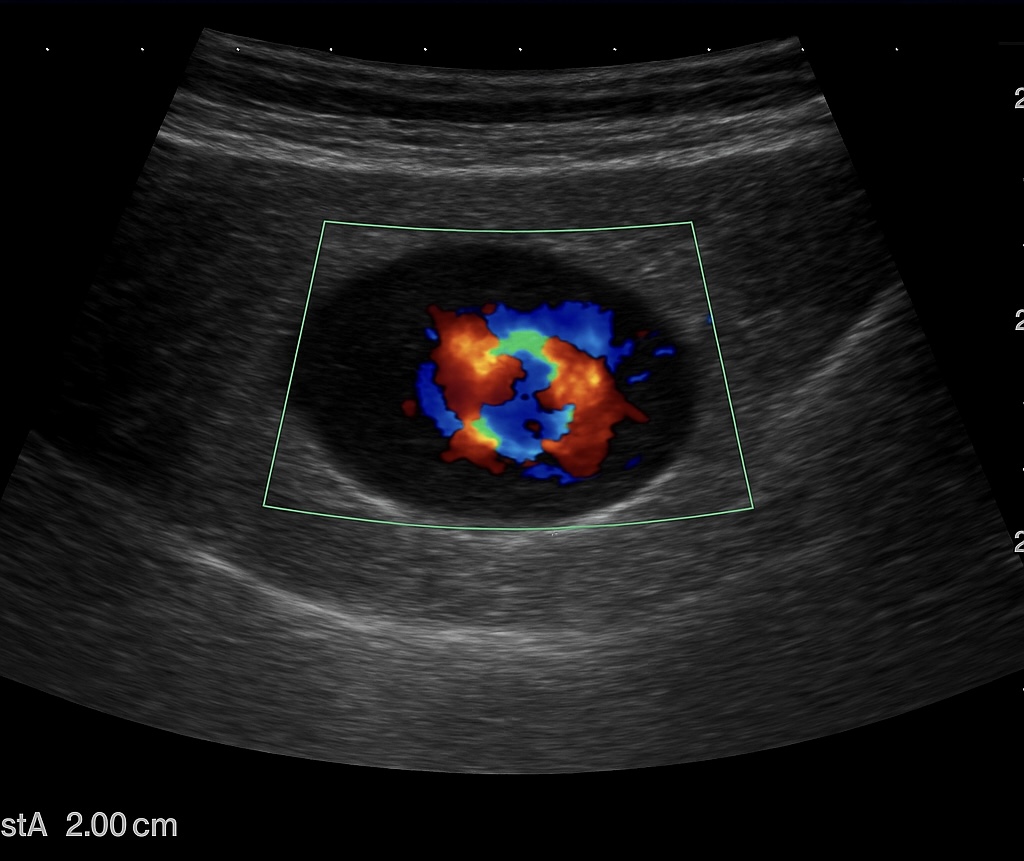

Ecografía musculoesquelética: lesión anecoica redondeada de aproximadamente 2 cm, con patrón yin-yang en Doppler color y flujo turbulento en Doppler espectral, compatible con pseudoaneurisma dependiente de rama arterial axilar superficial. No datos de bursitis, absceso o hematoma no vascularizado.